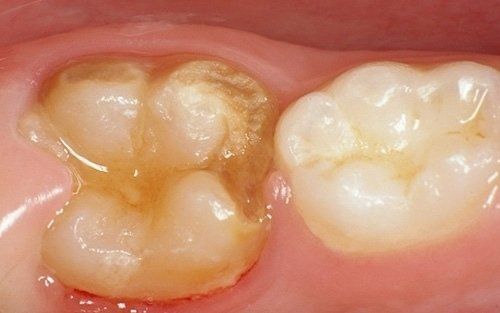

Despite the first signs having been noticed by practitioners at the end of the last century, we can consider the hypomineralisation of molars and incisors (M.I.H. - Molar Incisors Hypomineralisation) as a condition of children in the 2000s. It is characterised by insufficient mineralisation, especially of the first permanent molars, which appear with white-yellowish or brown spots and enamel that is very "porous," lacking the protective shield necessary for the health of these teeth. This leads to a greater tendency for decay, but above all, to structural breakdown of the affected areas under chewing load.